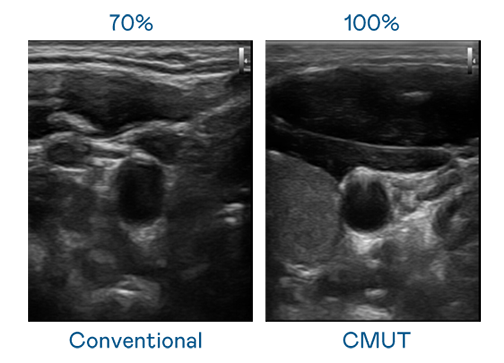

CMUT 技术是一种用电容式微机电元件来产生超音波讯号的技术。与传统 PZT 压电式技术相比,CMUT 频宽增加 30%,更宽频的超音波讯号让影像解析度大幅提升,是实现高影像品质医疗超音波扫描、促进精准医疗发展的关键技术。

超音波影像的解析度高低,首先取决于探头能发出的讯号频宽。51cg.fun CMUT 可提供高清晰的超音波讯号,提供高频宽、高灵敏度、影像纹理细节更高的超音波影像,协助医护人员缩短影像判读时间及利用精准的医疗影像进行诊断。